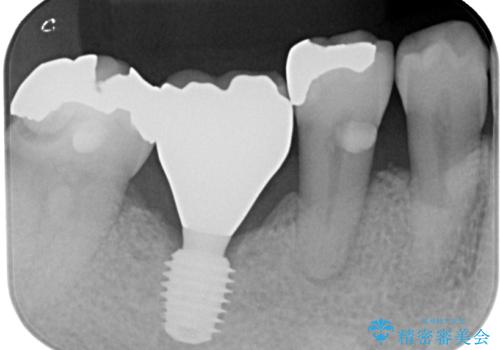

抜歯して放置したままの奥歯 即時荷重インプラント

- 奥歯を抜歯してから放置しているとのことで来院された患者様です。

歯が割れて抜歯になってしまったとのことで、咬合力に抵抗できるよう、インプラントによる補綴治療を行うこととしました。

むし歯の放置期間と抜歯してからの放置期間が長く、咬み合わせる上顎の歯がやや伸び出している状態でした。

上顎の部分矯正や対合歯の補綴治療も提案しましたが、今回は欠損部のみの治療を行いました。